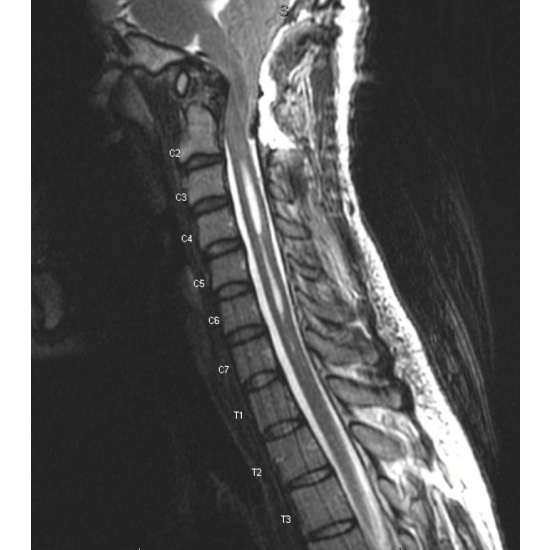

MRI cervical spine without contrast: Chiari 1.5 malformation with extensive syringomyelia of the cervical cord and partially imaged hydrocephalus of the fourth ventricle. Disc preserved in height and signal with no herniation or osteophyte complex C2-T1. Case Photo #5